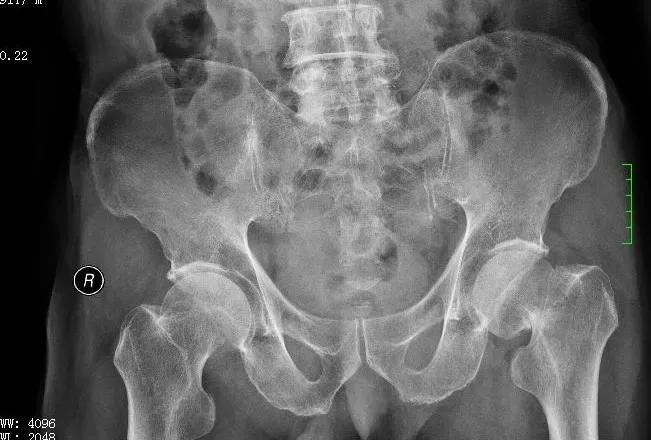

术前图

黄爷爷因摔伤致左侧股骨颈骨折到关节外科住院治疗。考虑到他已经91岁高龄,家人一开始倾向于选择保守治疗而非手术治疗。入院后,专家为他进行综合评估,征得家属及本人同意后,选择国内外快优康复的治疗标准,为他实施人工全髋关节置换术。在麻醉专家李喜松、黄红梅进行神经阻滞后,关节外科陆吉利、农家隆、陈俊、胡国芳四位专家共同为他进行手术。手术效果明显,术后第二天,患者在家人的协助下,可以使用助行器下床活动。术后第三、第四天,患者已能自行使用助行器下床活动。家属很激动地对医护人员说:“要是不做手术,老人家很痛苦,每天卧床不起,给家里人带来极大的护理负担。手术后,老人能自行活动,极大改善了生活质量。”